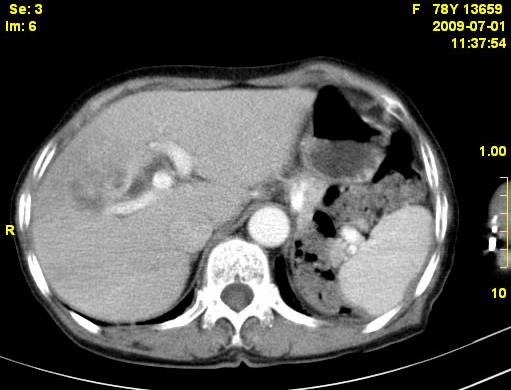

以下是引用zjzjr在2009-7-3 11:02:00的发言:[br]动脉期不均匀强化,门脉期及延迟期强化明显,肝门部见肿大淋巴结影,肝内胆管扩张.考虑肝右叶前段胆管细胞癌伴肝门淋巴结转移,胆内胆管扩张.慢性胆囊炎.

以下是引用dsl555在2009-7-4 10:59:00的发言:[br]考虑肝右叶前段胆管细胞癌伴肝门淋巴结转移,胆内胆管扩张.慢性胆囊炎. [br][br]支持。